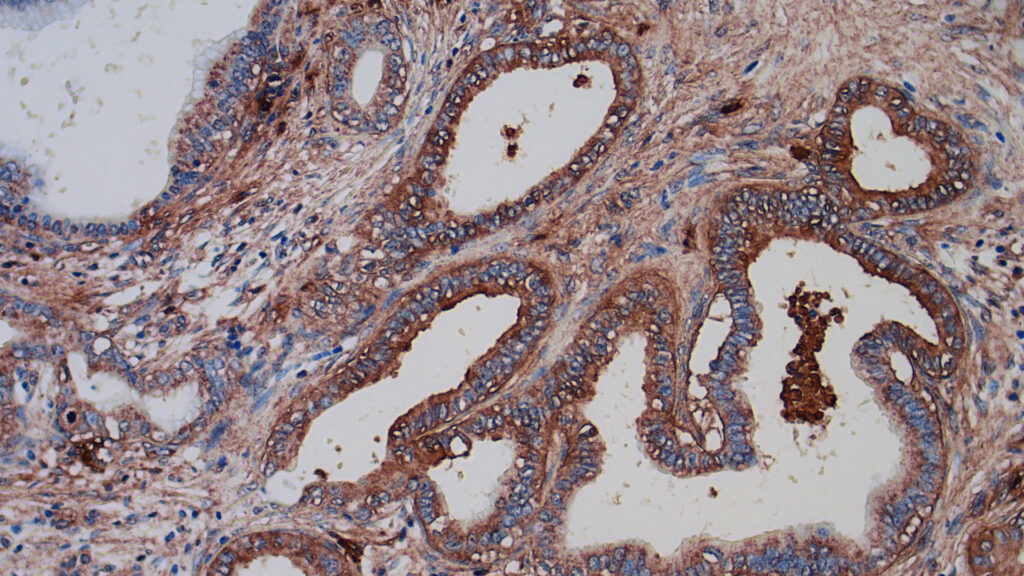

Immunohistochemical staining of an SRI molecular guidance system in human pancreatic tissue.